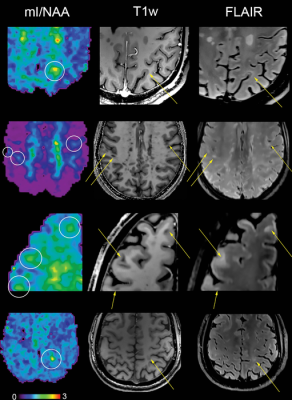

Metabolic maps showing the ratio of myo-inositol to N-acetylaspartate (mI/NAA) clearly depict small subcortical or juxtacortical lesions (circles) that appear inconspicuous at T1-weighted MRI (T1w)/fluid-attenuated inversion-recovery (FLAIR) imaging (indicated with arrows in three participants with multiple sclerosis). Image courtesy of Radiological Society of North America

Lesions to the brain’s signal-carrying white matter are the most readily detectable manifestation of MS on MRI. The lesions, linked to the loss of the protective coating around white matter fibers called myelin, represent only macroscopic tissue damage. A means to find changes in the brain at an earlier microscopic or biochemical stage would be beneficial.

The results showed reduced levels of an amino acid derivative called N-acetylaspartate (NAA) in patients with MS. Lower levels of NAA have been linked to impaired integrity of neurons in the brain. People with MS also showed elevated levels of myo-inositol (MI), a compound involved in cell signaling. Higher levels are indicative of substantial inflammatory disease activity.

The metabolic alterations in normal-appearing white matter and cortical gray matter were associated with disability.